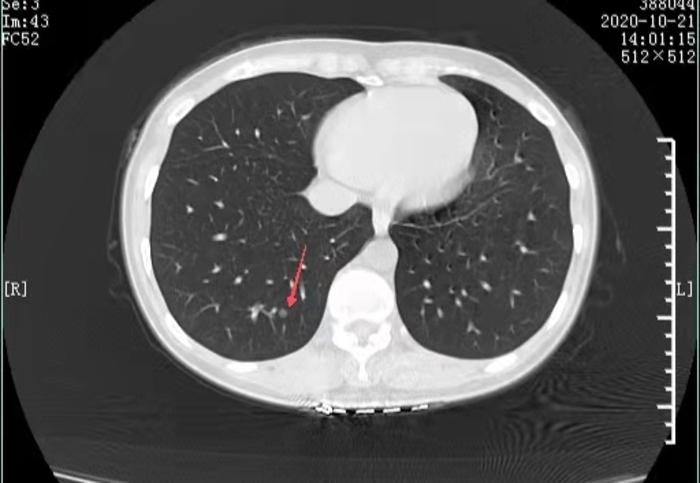

我一看片子,又看了报告上结节的大小,这不就从4mm变成了5mm,是真长大了,还是测量误差都还说不准呢?基本没什么变化。又是一个因为发现肺结节而过度紧张的典型案例。